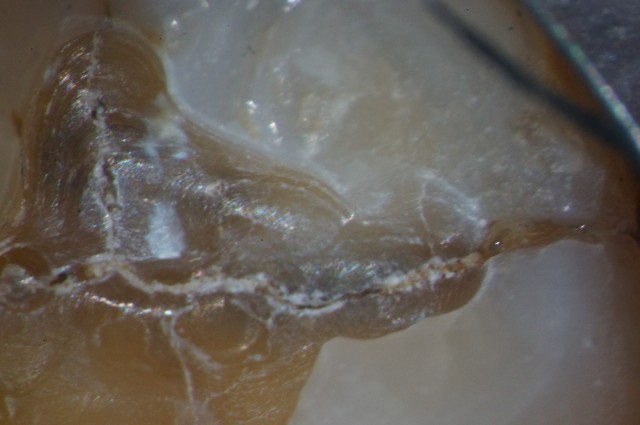

Our plan and hope was to replace the failing alloy with a new composite, assuming of course we found no fracture inside the tooth. Unfortunately, upon preparation, here is what we found.

As you can see, there were multiple fractures inside this tooth. To add to the concern, this tooth is also the patient’s first point of contact in centric relation.